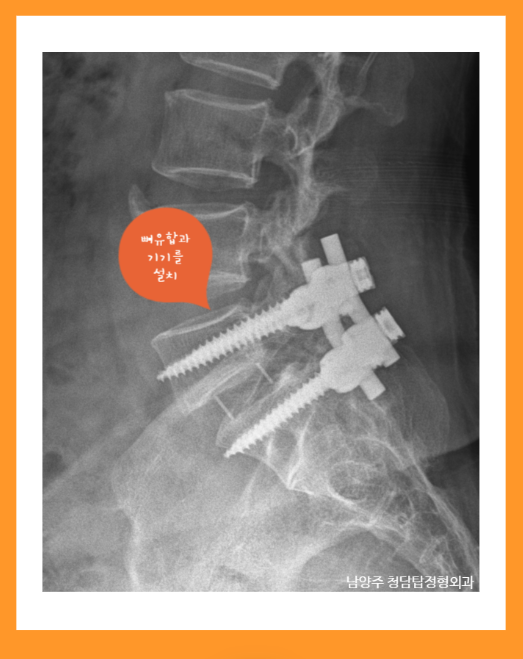

3. 안정화 치료

척추 분리증 및 구조적 불안정을 기기 설치 및 유합술로 교정.